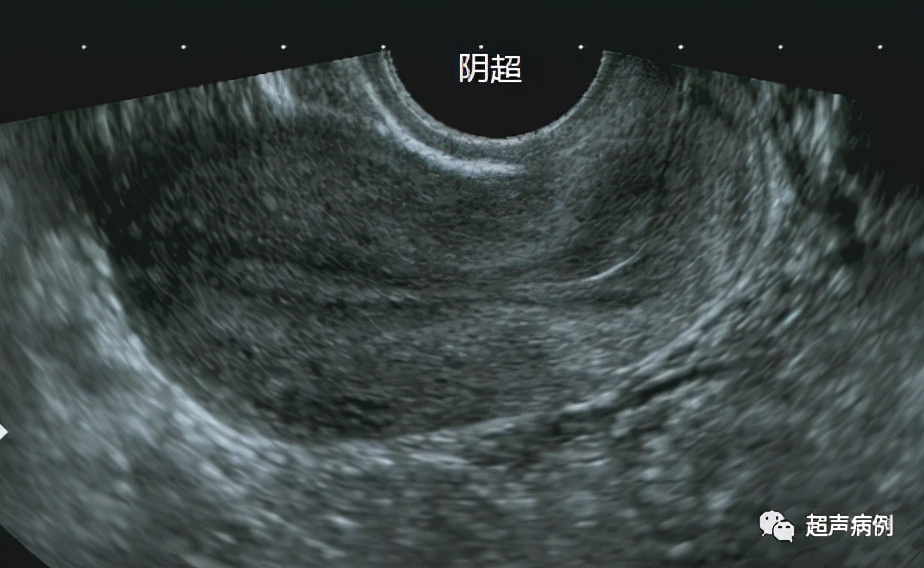

阴道超声检查的是将腔道探头经阴道直接接触子宫及附件的一种超声检查(当然会对探头套个保护套,避免不卫生)。

阴超检查方式